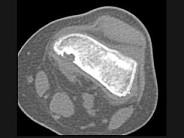

问题 男,12岁,大腿下部间歇性疼痛,劳累后加重,结合图像,最可能的诊断是?(?)

选项 A.纤维性骨皮质缺损 B.干骺端结核 C.骨样骨瘤 D.邻皮质软骨瘤 E.非骨化性纤维瘤

答案 A